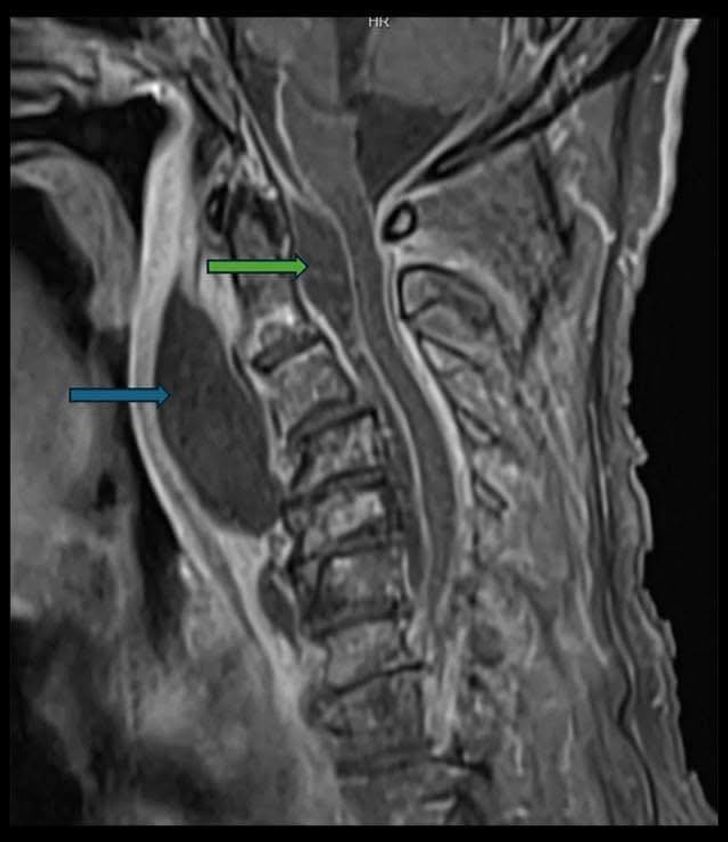

แพทย์ในห้องฉุกเฉินพบว่าลิ้นไก่ถูกดันมาด้านหน้า ผนังคอด้านหลังบวมผิดปกติ และมีเสียงหายใจคล้ายกรนทั้งที่ไม่ได้หลับ จึงเร่งตรวจเอกซเรย์คอมพิวเตอร์และ MRI พบฝีหนองขนาดใหญ่ใน “ช่องหลังคอ” หรือ retropharyngeal space ซึ่งกดทับทางเดินหายใจจนเหลือช่องว่างเพียงเล็กน้อย เสี่ยงต่อการอุดกั้นทางเดินหายใจในเวลาอันสั้น

ที่น่ากังวลยิ่งกว่านั้น แพทย์พบว่าการติดเชื้อมีต้นตอมาจากฟันผุที่ลุกลามผ่านกระดูกขากรรไกร ต่อมน้ำเหลือง และเข้าสู่ช่องหลังคอ ก่อนแพร่กระจายไปยังโพรงเยื่อหุ้มไขสันหลัง หรือ epidural abscess ซึ่งเป็นภาวะอันตรายถึงชีวิต